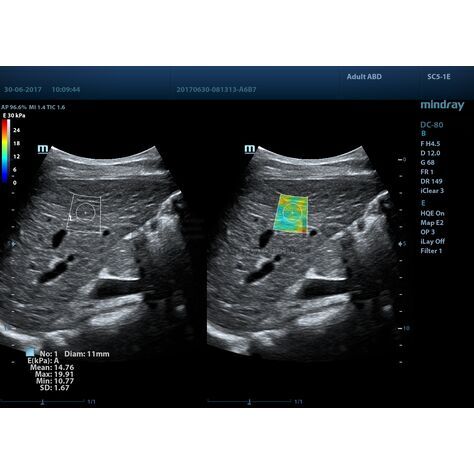

STE (Sound Touch Elastography)

STE интегрирована с эксклюзивной технологией Ultra-Wide Beam Tracking от Mindray для двумерной эластографии сдвиговой волной в реальном времени. Специализированные измерительные инструменты позволяют проводить количественный анализ модуля упругости с высокой точностью.